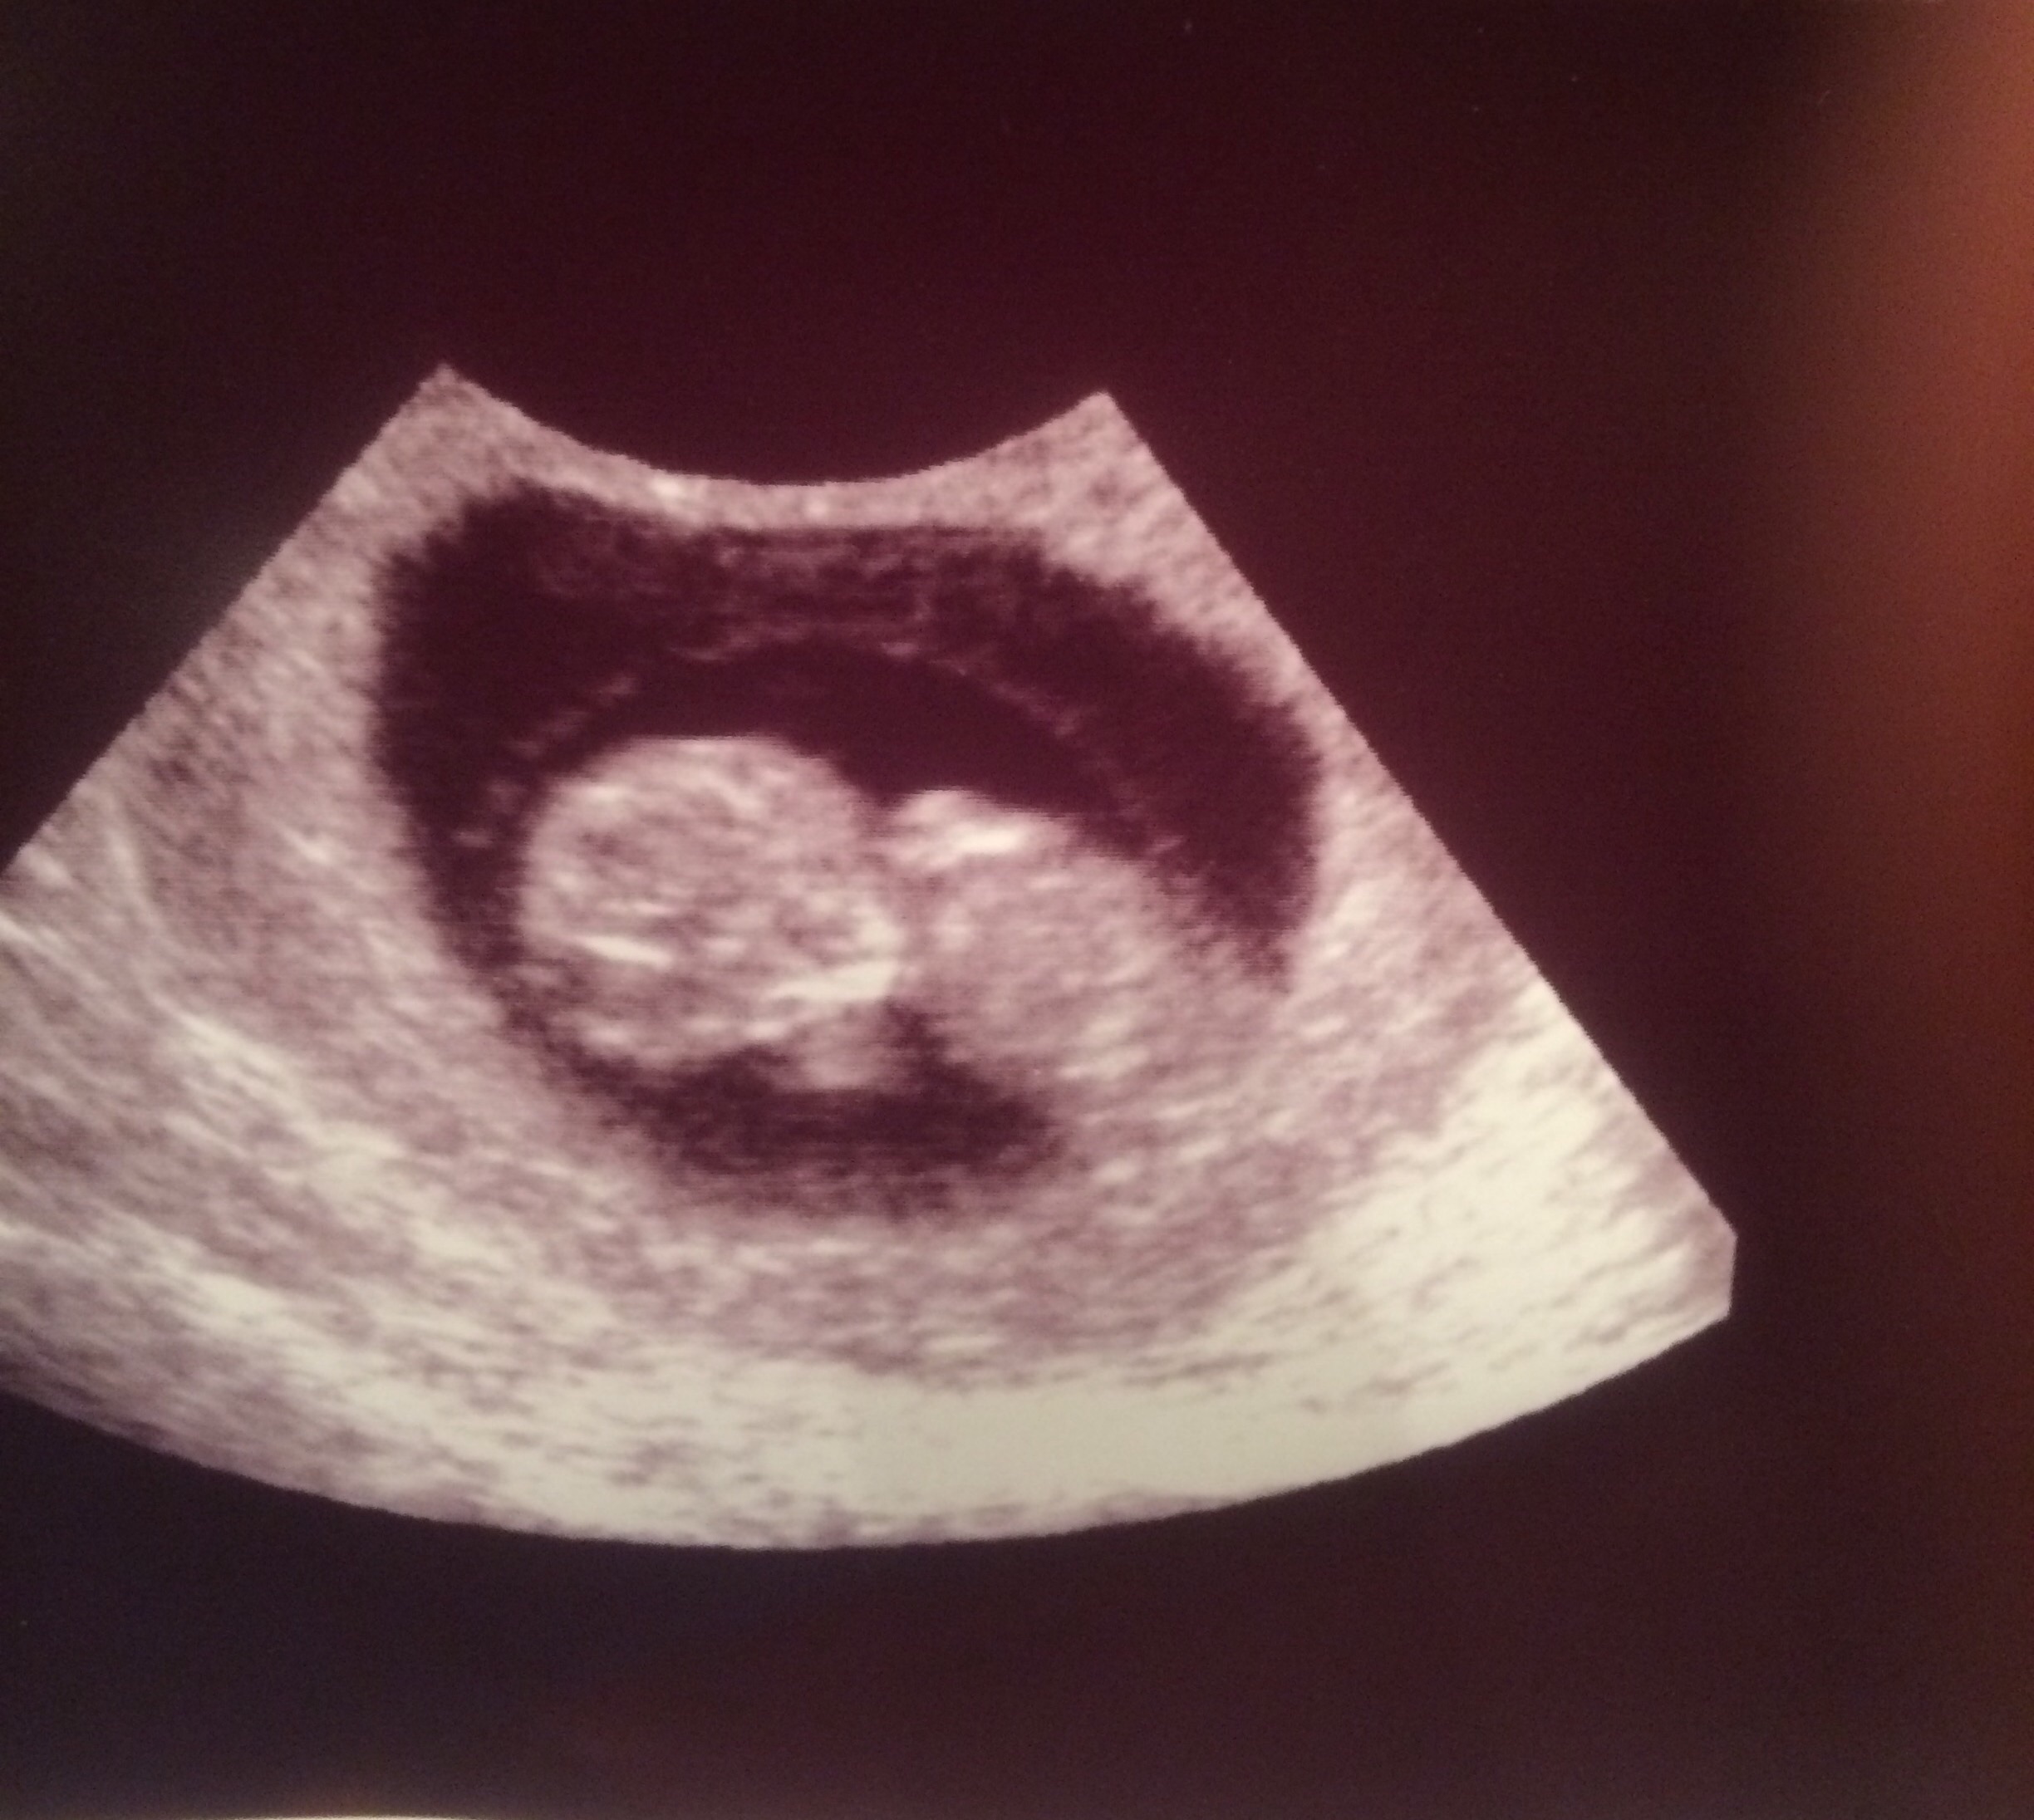

I don't have my pictures scanned in, but I guess I need too now! Wow I can't believe how baby like it looks at 9 weeks! That is insane. I got to see the heart beat, but my OB said we would listen next time!!! So excited!